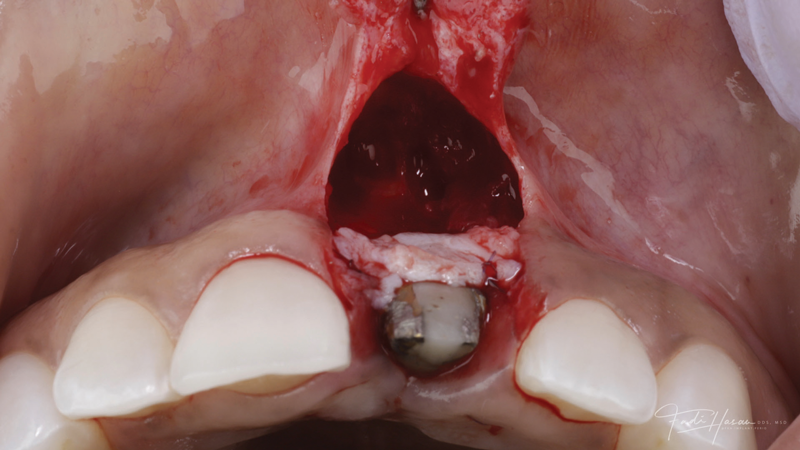

(4.) The crown was removed, and a partial thickness flap was reflected using a papilla-sparing incision design, which revealed that the implant was positioned too far facially and that its body was visible through a very thin layer of bone.

Figure 4

The patient in this case had undergone implant therapy at the site of tooth No. 9 and was restored with a cement-retained restoration more than 5 years prior. At presentation, the site demonstrated a peri-implant soft-tissue dehiscence that extended approximately 3-mm apical to the gingival margin of tooth No. 8. Thin and erythematous marginal tissue was evident at the zenith (Figure 2). The crown was removed, and a partial thickness flap was reflected using a papilla-sparing incision design. This revealed that the implant was positioned too far facially and that its body was visible through a very thin layer of bone (Figure 3 and Figure 4). The first objective of treatment was to minimize the facial extent of the emerging abutment and crown. To accomplish this, the facially positioned abutment and implant crown margin were both recontoured. The second treatment objective was to provide additional supracrestal soft tissue that would more adequately maintain the peri-implant margin. The tuberosity was selected as a donor site due to its dense, high-quality connective tissue, low propensity for shrinkage, and association with minimal patient discomfort. Once the graft was secured (Figure 5 through Figure 7), the flap was coronally positioned (Figure 8). After a healing period of 2 weeks, the margin of tooth No. 9 exhibited an ideal position in relation to its contralateral counterpart and demonstrated increased soft tissue thickness (Figure 9). Three months postoperatively, further healing had improved the esthetics and the position of the margin had been maintained (Figure 10).